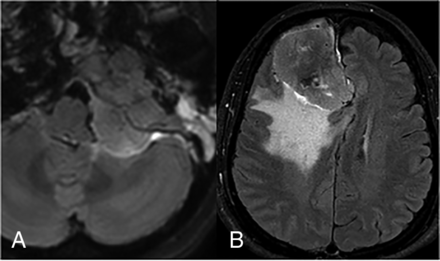

Most meningiomas exhibited complete rim enhancement of the tumor-brain interface on CE-FLAIR sequences (91/102, 89.2%) (Fig 2), which was significantly higher than that in malignant dural-based tumors (2/31, 6.5%) (P < .001). Additionally, meningiomas frequently showed hyperostosis (76/102, 74.5%), marrow edema (76/102, 74.5%), and homogeneous enhancement on T1WI (75/102, 73.5%), features that were all significantly different compared with malignant dural-based tumors (P < .001), which demonstrated hyperostosis (0/31, 0%), marrow edema (6/31, 19.4%), and homogeneous enhancement on T1WI (9/31, 29%). In contrast, malignant dural-based tumors that demonstrated cortical breakthrough (21/31, 67.7%) and leptomeningeal enhancement (10/31, 32.3%), absence of a dural tail sign (6/31, 19.4%), hypointensity on T2WI (8/31, 25.8%), and heterogeneous enhancement on T1WI (22/31, 71%) were significantly different compared with meningiomas (P < .001), which showed cortical breakthrough (5/102, 4.9%), leptomeningeal enhancement (0/102, 0%), absence of a dural tail sign (2/102, 2%), hypointensity on T2WI (4/102, 3.9%), and heterogeneous enhancement on T1WI (27/102, 26.5%). A summary of the MR imaging findings of meningiomas and malignant dural-based tumors is presented in the Online Supplemental Data.

CE-FLAIR rim sign in meningiomas at the cerebellomedullary cistern (A) and parafalcine region (B).